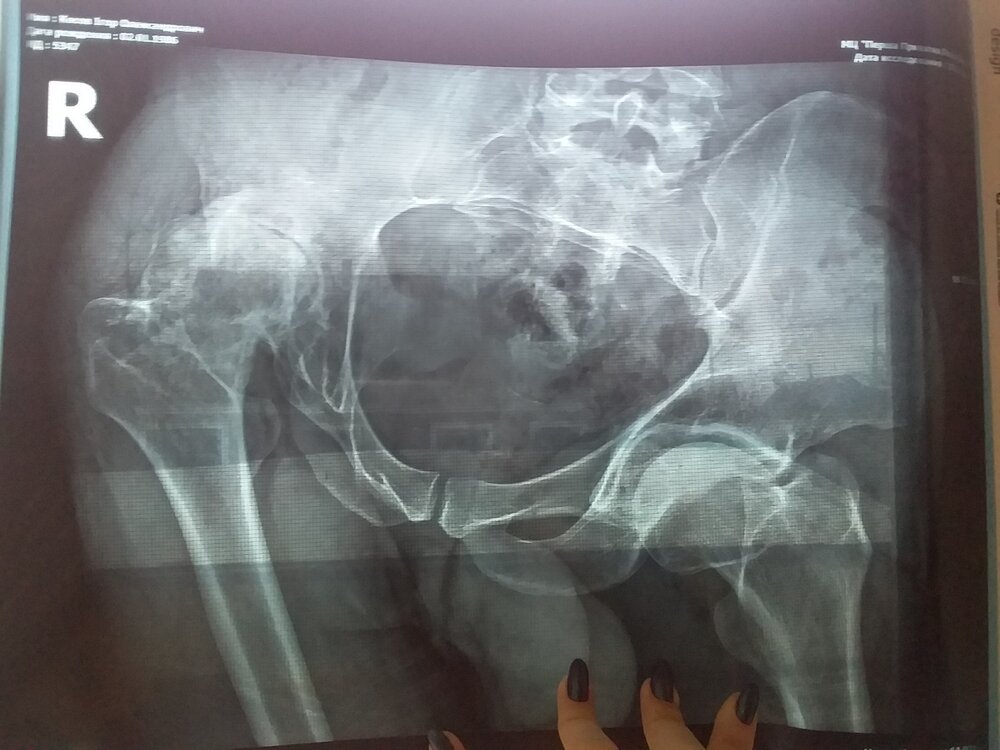

monolithgidrostrou Опубліковано: 23 січня 2021 Поділитись Опубліковано: 23 січня 2021 Всем здраствуйте! Долго решался написать. Мне 35, женат, двое детей, работаю сварщиком. Инвалид детства 3гр. Правая нога короче левой примерно 14-16см Ездил на консультацию в Киев,Харьков,Черновцы В Киеве операция +- 120000 грн В Харькове 90000 грн В Черновцах, клиника энгельхольм, там от 4400 до 5300 у.е, дают гарантию 35 лет Но как я не работаю, как я не откладываю, не получается собрать на операцию, собрал с горем пополам 60000 грн. Мечта всетаки поехать в Черновцы, прошу Вас помочь, в проведении операции.Всем спасибо! 4323387027105306-kosov2 (6).pdf 1 Посилання на коментар Поділитися на інших сайтах More sharing options...

monolithgidrostrou Опубліковано: 25 січня 2021 Автор Поділитись Опубліковано: 25 січня 2021 Фото Посилання на коментар Поділитися на інших сайтах More sharing options...